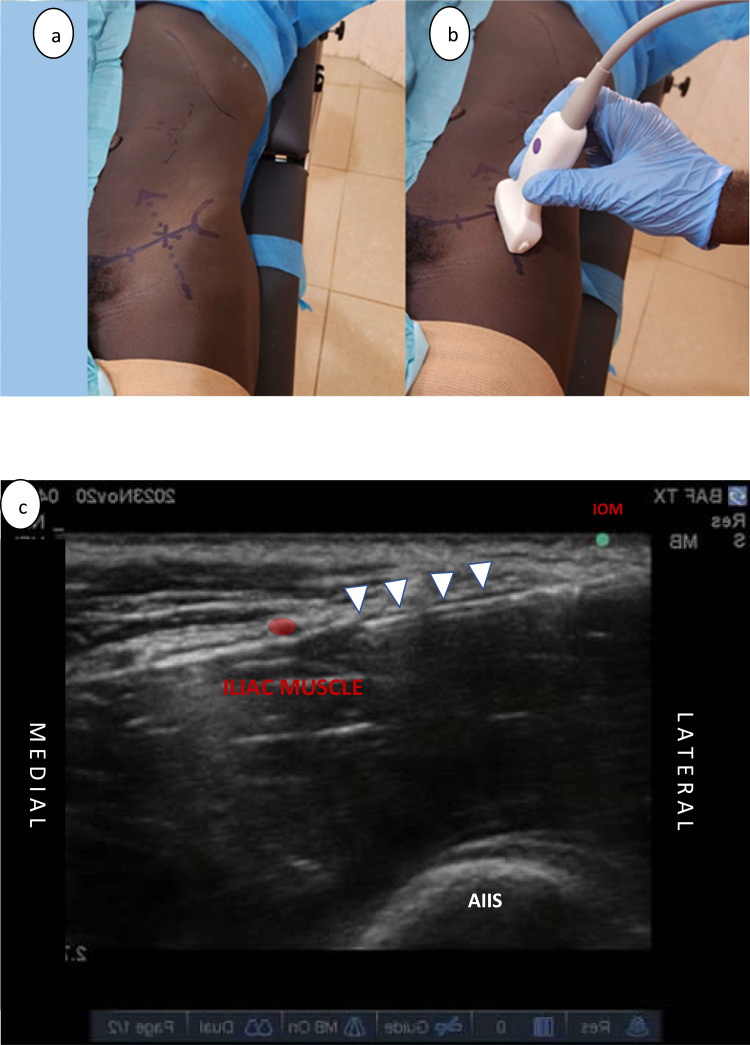

Purpose: The management of unstable patients with weapon-wounded lower limb vascular injuries presents significant anesthetic challenges. Regional anesthesia blocks, which combine lumbar and sacral plexus blocks, or their respective branches, minimize systemic effects and are deemed appropriate for high-risk patients requiring lower limb surgery. This case series aims to share our preliminary experiences with a combined anesthetic technique-sciatic nerve (SN), posterior femoral cutaneous nerve (PFCN), and supra-inguinal fascia iliaca (SIFI) blocks -in patients sustaining weapon wounds and undergoing lower limb vascular injury repair in austere environments.

Patients and methods: Seven patients with lower limb vascular injuries resulting from weapons who required surgery at district hospitals supported by the International Committee of the Red Cross were included in this study. Included patients underwent surgery for vascular repair and debridement using a combined nerve block technique involving the SN, PFCN, and SIFI blocks between May and December 2023. The blocks were administered using a 1:1 mixture of 1% lidocaine and 0.5% levobupivacaine.

Results: The combined block technique for the Sciatic Nerve (SN), Posterior Femoral Cutaneous Nerve (PFCN), and the Supra-Inguinal Fascia Iliaca (SIFI) were performed without complications in all patients. Three of the patients received light sedation prior to the initiation of the block procedure. All surgeries were completed successfully without the need for additional analgesics or conversion to general anesthesia.

Conclusion: The combined block technique for the Sciatic Nerve (SN), Posterior Femoral Cutaneous Nerve (PFCN), and the Supra-Inguinal Fascia Iliaca (SIFI) appears to be a safe anesthetic option for unstable or high-risk patients requiring lower limb surgery. Further research with a larger cohort is necessary to validate our findings and to potentially standardize this approach.